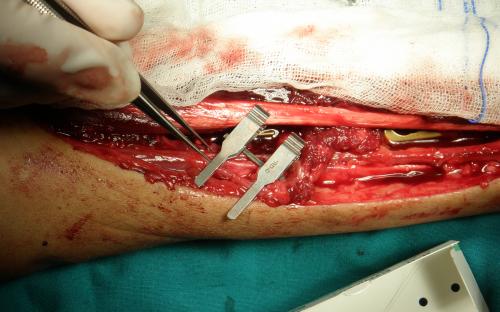

Άντρας 21 ετών υπέστη διπολικό κάταγμα της κερκίδας και κάταγμα της ωλένης, που αντιμετωπίστηκε σε περιφεριακό νοσοκομείο. 9 μήνες μετά διαπιστώθηκε ψευδάρθρωση της κερκίδας με οστικό απόλυμα 6,5 εκ. Αντιμετωπίστηκε με τη χρήση αγγειούμενης περόνης, η οποία γεφύρωσε το οστικό έλλειμμα της κερκίδας.